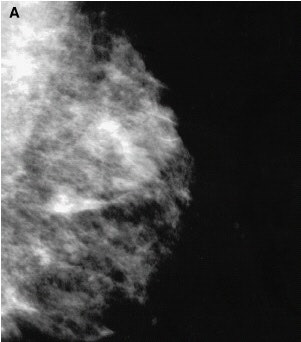

Detection of unsuspected cancer with high-resolution breast-specific gamma camera in 33-year-old woman, 2 years after lumpectomy and radiation therapy for infiltrating ductal carcinoma of the right breast. Mediolateral oblique and craniocaudal mammograms (A and B) of the left breast show normal findings.